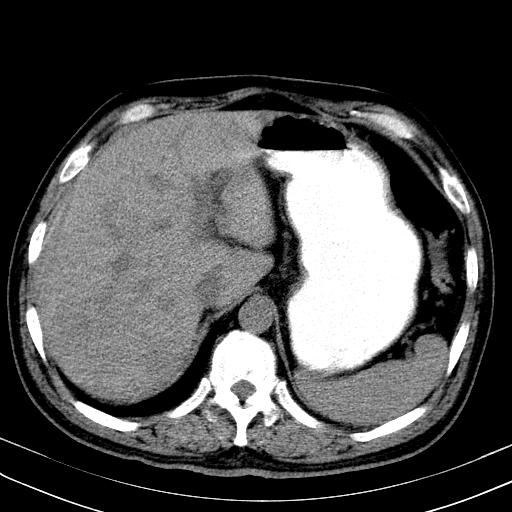

先行ct平扫,纵膈内多发软组织影,ct值约为36hu,以下为增强扫描和腹部平扫。

还见胃窦壁增厚!转移亦有可能!

大家看看肝脏右叶片状低密度影是什么改变啊?

淋巴瘤?肝脏请增强后说啊

多发肿大淋巴结影,肝内改变需结合强化观察

多发肿大淋巴结影,肝内改变需结合强化观察。